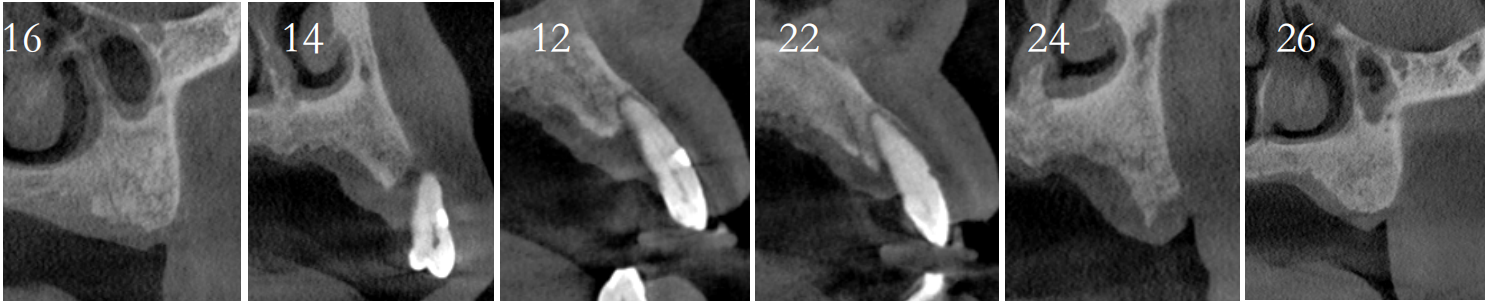

CT检查:后牙余留骨量高度10-12mm,前牙骨高度12-14mm,宽度均大于6mm。

方案设计:

导板制作完成:

导板引导下种植手术: